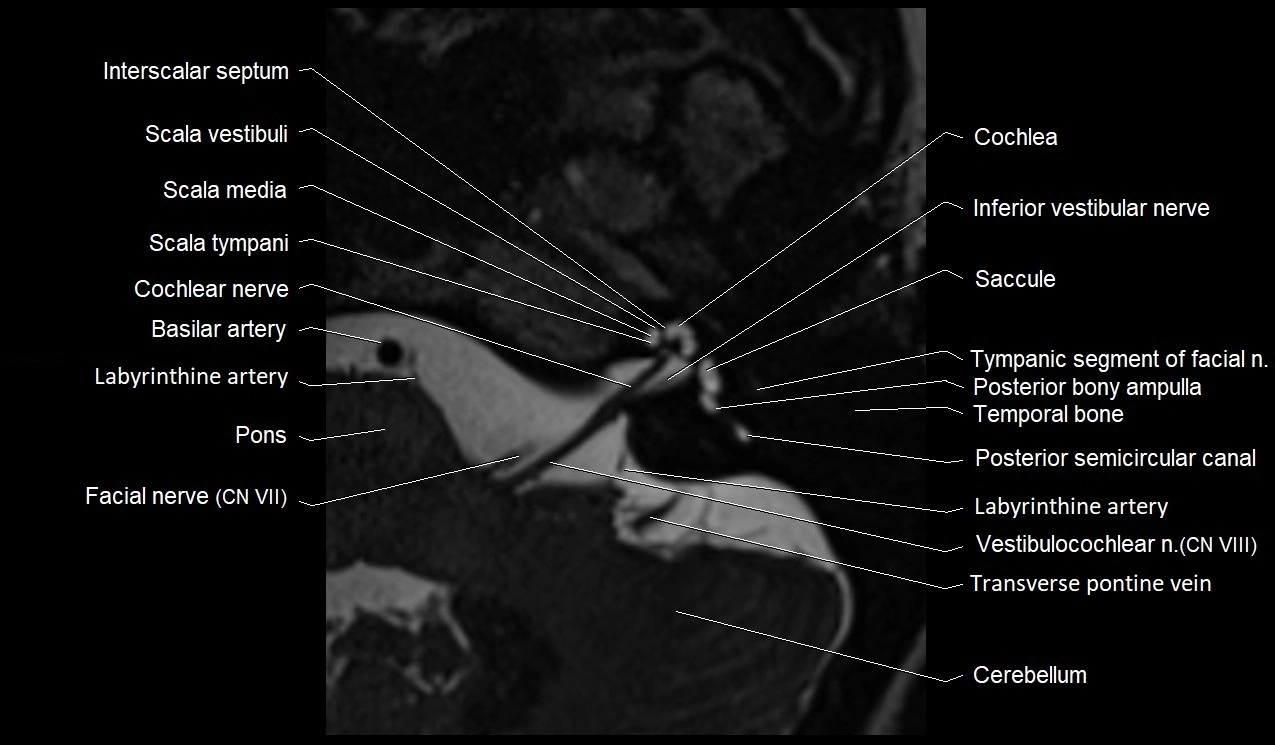

MRI images

image